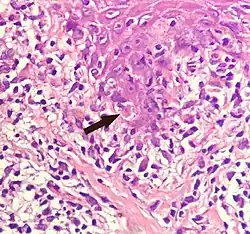

Civatte body

A Civatte body (named after the French dermatologist Achille Civatte, 1877–1956)[36] is a damaged basal keratinocyte that has undergone apoptosis, and consist largely of keratin intermediate filaments, and are almost invariably covered with immunoglobulins, mainly IgM.[37] Civatte bodies are characteristically found in skin lesions of various dermatoses, particularly lichen planus and discoid lupus erythematosus.[37] They may also be found in graft-versus-host disease, adverse drug reactions, inflammatory keratosis (such as lichenoid actinic keratosis and lichen planus-like keratosis), erythema multiforme, bullous pemphigoid, eczema, lichen planopilaris, febrile neutrophilic dermatosis, toxic epidermal necrolysis, herpes simplex and varicella zoster lesions, dermatitis herpetiformis, porphyria cutanea tarda, sarcoidosis, subcorneal pustular dermatosis, transient acantholytic dermatosis and epidermolytic hyperkeratosis.[37]